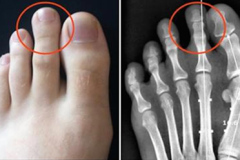

Создана первая в мире говорящая сексуальная кукла (Видео) Гороскоп красоты: особенности внешности разных знаков зодиака Вот что КАТЕГОРИЧЕСКИ нельзя делать в чистый четверг Этот ребенок умер ещё во чреве матери. Однако то, что произошло дальше — самое н... Внебрачная дочь Джеки Чана попыталась покончить с собой 13 скрытых признаков того, что вы не так здоровы, как вам кажется Считается, что самый смертоносный напиток в мире, он может убивать вас менее чем... Какой вы цветок по знаку Зодиака Ксения Бородина впервые показала нос после возможной ринопластики (Фото) Если доску для утюга накрыть фольгой, гладить можно в 2 раза быстрее! Вот почему Дочь Майкла Джексона отметила 19-летие, поедая бургеры на обочине (фото) Ей пришлось отдать ребенка,которого она считала своим- ужас! В роддоме 25 лет на... Как понять, что он тебя любит: 10 верных признаков Что будет, если три года совсем не подстригать ногти (Фото) Указательный палец длиннее других? Вот что это может сказать о Вашем характере В армии Таиланда начался весенний призыв Не виновата она! Хлое Севиньи случайно показала лишнее в очень короткой юбке (Ф... 10 видов женщин, от которых всегда сбегают мужчины Будь стильной этим летом: 8 основных модных тенденций 2017 года Ожидания и реальность: фанатка Кейт Миддлтон копирует все образы герцогини Что на этой картинке кажется вам наиболее странным? Мой ласковый и нежный зверь: знаменитости, которые встречались с мужчинами-тиранами ОПРЕДЕЛЯЕМ ИМИДЖ ПО ЗНАКУ ЗОДИАКА Она родила близнецов. Но один из них на 2 года старше второго Принимайте этот мощный сироп, чтобы растворить камни в почках Весь персонал больницы пребывал в шоке, узнав, что бабушка хотела сделать с внуком ВРЕМЯ ДЛЯ ПРЕДСКАЗАНИЙ: ВЫБЕРИТЕ ФРУКТ И УЗНАЙТЕ СВОЕ БУДУЩЕЕ Как вы думаете, кто из этих малышей — девочка? Мать намазала 3-месячного малыша солнцезащитным кремом! И вот что с ним стало Стать королевой можно во всем